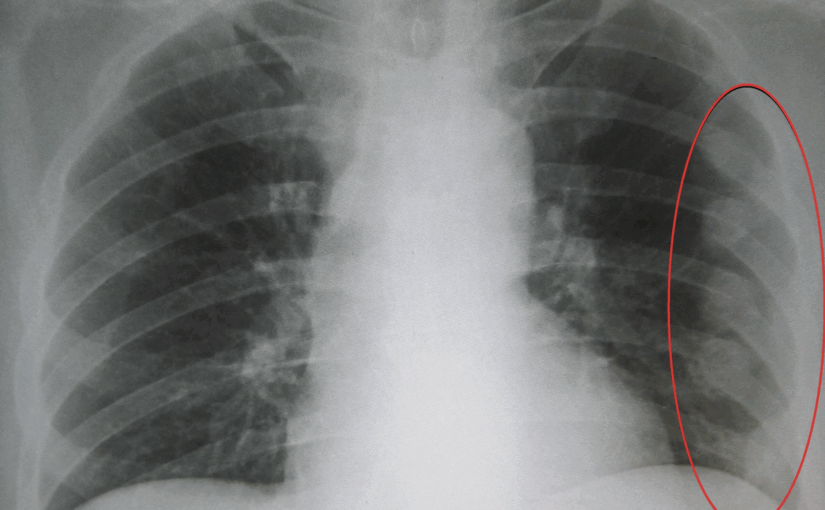

Tras la agresión, la víctima permaneció en su hogar hasta que sus propios hermanos tomaron conocimiento de lo sucedido y lo trasladaron al hospital local. La médica de guardia constató las lesiones, incluyendo un traumatismo en la región orbitaria izquierda con sangrado y la fractura de la última costilla del hemitórax derecho con un leve desplazamiento. Como resultado de la intervención policial, uno de los hermanos agresores fue detenido, mientras que el otro permanece en libertad bajo medidas sustitutivas de la prisión preventiva. La causa se encuentra en manos del fiscal Enzo Rangone, perteneciente a la IV Circunscripción del Ministerio Público Fiscal.

Foto ilustrativa